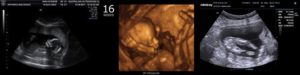

Женщина может получить протокол и фото результатов УЗИ на 16,17 неделе беременности. На основании данных врач формирует биофизический профиль плода.

Плод свободно передвигается в амниотической жидкости. На крохотных ручках и ножках сформировались пальчики, которые мама сможет увидеть на фото УЗИ. Ребёнок демонстрирует великолепную мимику, рефлекторно гримасничая и улыбаясь. Зевающий малыш – прекрасный момент, который может запечатлеть фотография.